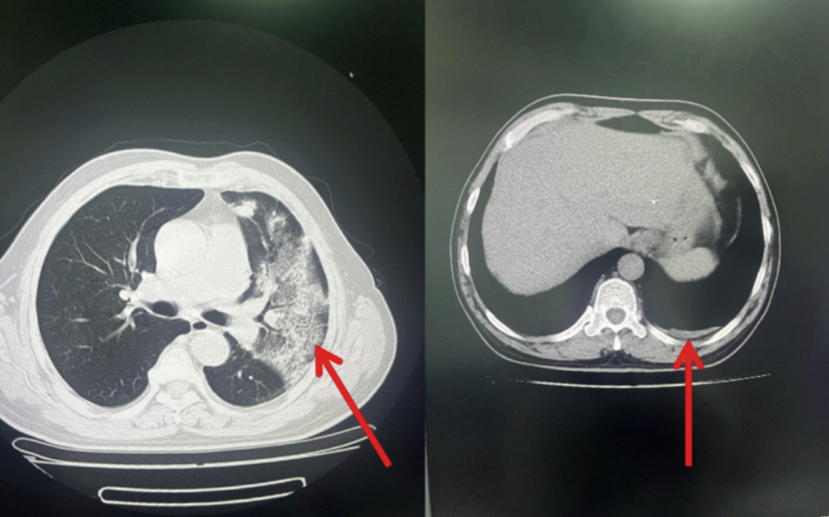

胸部CT:左肺上叶病灶明显减小,左侧胸腔积液消失。患者病情好转,于9月20日出院(见图4)。

图4:左肺上叶病灶明显减小,左侧胸腔积液消失